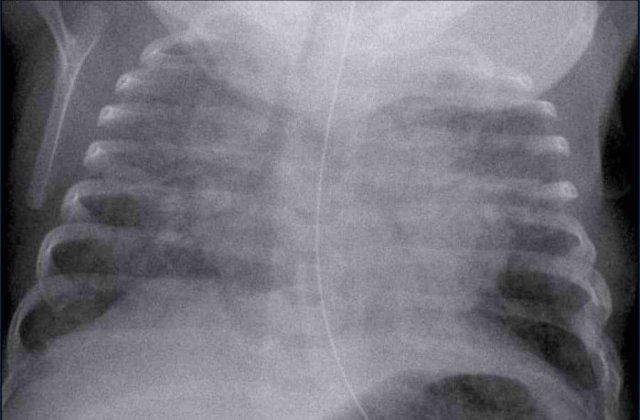

Trẻ sơ sinh 41 tuần tuổi thai. 24 giờ tuổi.

Suy hô hấp, không hỗ trợ thở máy

Image

- Marked

hyperinflation of both lungs - Increased

vascular markings and interstitial markings - Some interfissural fluid (arrow).

Spontaneous improvement within 48 hours.